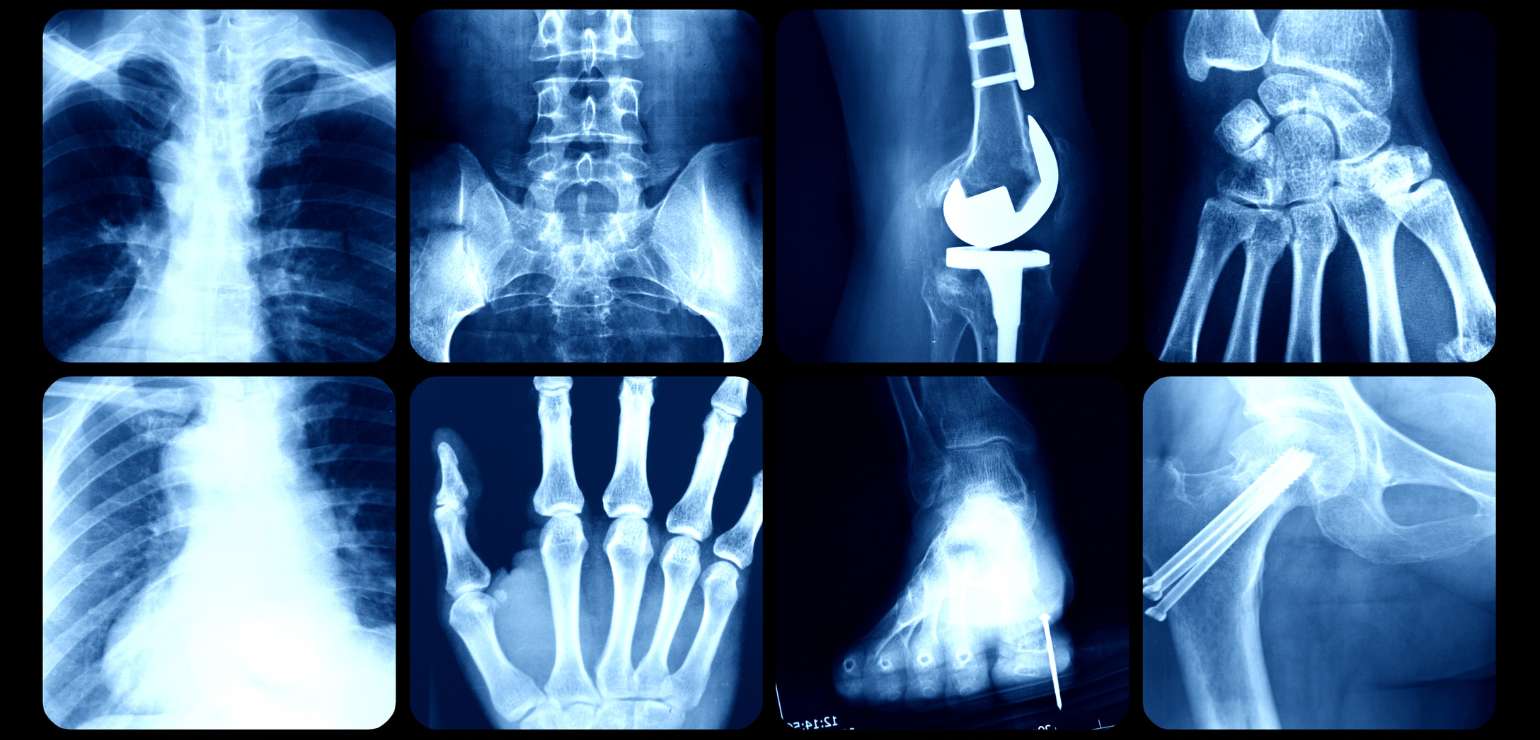

X-ray

What is an X-ray?

An X-ray is performed to get images of any bone in any part of the body. This determines the problems in a bone at a very basic level making it the fastest way of diagnosing the issue.